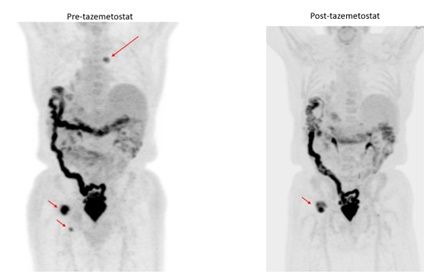

A female in her early 80s* presented for management of relapsed low grade follicular lymphoma. She had an extensive medical history, including coronary artery disease status post stent placements, cerebrovascular stroke without residual motor or sensory deficits, diabetes, and chronic kidney disease. She initially presented with right inguinal mass and right lower extremity edema. Work-up at the time revealed FDG avid bulky adenopathy in the inguinal, pelvic, retroperitoneal, and bilateral axillary areas. The max SUV was 9 in the pelvic area and a biopsy from a pelvic lymph node was consistent with follicular lymphoma, low grade 1-2. She received therapy with mini-R-CHOP, which she tolerated reasonably well and achieved complete remission. Three years later, she was found to have relapsed disease when she again developed right lower extremity edema and imaging revealed adenopathy in the inguinal and pelvic area. A restaging PET revealed FDG-avid adenopathy in the inguinal and pelvic regions. She received radiation therapy to the pelvic and inguinal lymph nodes and was again in remission which lasted 12 months when she was found to have recurrent adenopathy in the axillary and retroperitoneal regions on surveillance imaging. She remained on active surveillance, but then developed left lower extremity edema and was found to have recurrent left pelvic adenopathy. A repeat lymph node biopsy was done which showed follicular lymphoma grade 1-2 without evidence of transformation and EZH2 testing came back as EZH2-wild type. Given her age, comorbid conditions, and performance status, she was deemed not a good candidate for further chemoimmunotherapy and was started on oral tazemetostat. She achieved a partial remission for the next 14 months. Eventually she developed recurrent disease with FDG-avid adenopathy with SUV 17 and a lymph node biopsy showed transformation to diffuse large B-cell lymphoma. She was subsequently treated with an anti-CD19 monoclonal antibody and achieved a partial remission for 4 months, but then relapsed and received hospice care.